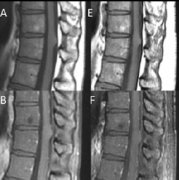

【高难度脊髓脑干胶质瘤95%以上切除案例】2019年,INC国际神经外科医生集团秉着国内外学术技术交流的初心,曾多次组织旗下国际神经外科顾问团(WANG)...

【脑干胶质瘤案例】手术辅助放化疗,较大脑干胶质母细胞瘤术后4年未复发,病史摘要:34岁男性,有6个月的左侧面部感觉丧失、听力障碍、轻度面瘫和右...